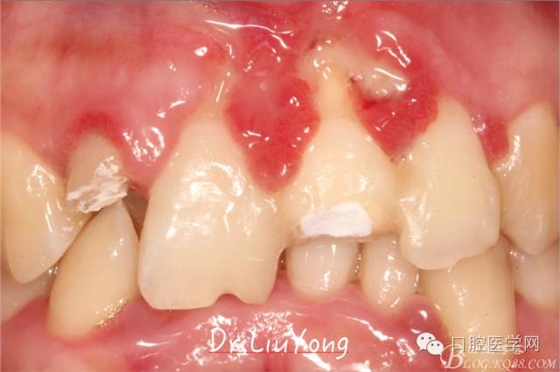

松動牙固定一月后拆除,A1-B2無明顯動度,但牙齦紅腫加重,給予全口齦上下潔治刮治術(shù),上藥,醫(yī)囑加強(qiáng)口腔衛(wèi)生,氯己定漱口液含漱。

術(shù)后兩周復(fù)查,牙齦紅腫明顯好轉(zhuǎn),探診不出血,但是此時A1唇側(cè)牙齦角形退縮1.5mm,B1唇側(cè)牙齦退縮3.5mm,B1遠(yuǎn)中牙齦乳頭萎縮明顯,B2近中牙齦萎縮約1mm,且A1B1B2牙齦退縮處角化牙齦幾乎缺失,同時上唇系帶直接牽拉于B1齦緣。患者為高笑線女性,露齦笑,由于存在前牙區(qū)牙齦的高度嚴(yán)重不對稱及前牙牙冠過長的問題,因此嘗試通過膜齦手術(shù)改善患牙牙齦退縮。通過術(shù)前分析,A1唇側(cè)牙齦退縮屬于Miller分類第一類, B1唇側(cè)牙齦退縮屬于Miller分類第3類(B1遠(yuǎn)中牙齦乳頭為2類,Nordland and Tarnow分類法),B2唇側(cè)牙齦退縮屬于Miller分類第3類,由于擬采用冠向復(fù)位瓣的方式治療牙齦退縮,因此需要先行上唇系帶修整術(shù),解除上唇系帶帶來的過大牽引力。

潔治刮治后2周,如上圖